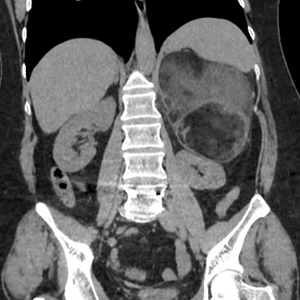

Agosto 2025. Sanatorio de la Cañada Pte femenino de 52 años, Mc: dolor abdominal difuso, App: hta, Mh: Losartan, A qx: osteosíntesis lumbar.